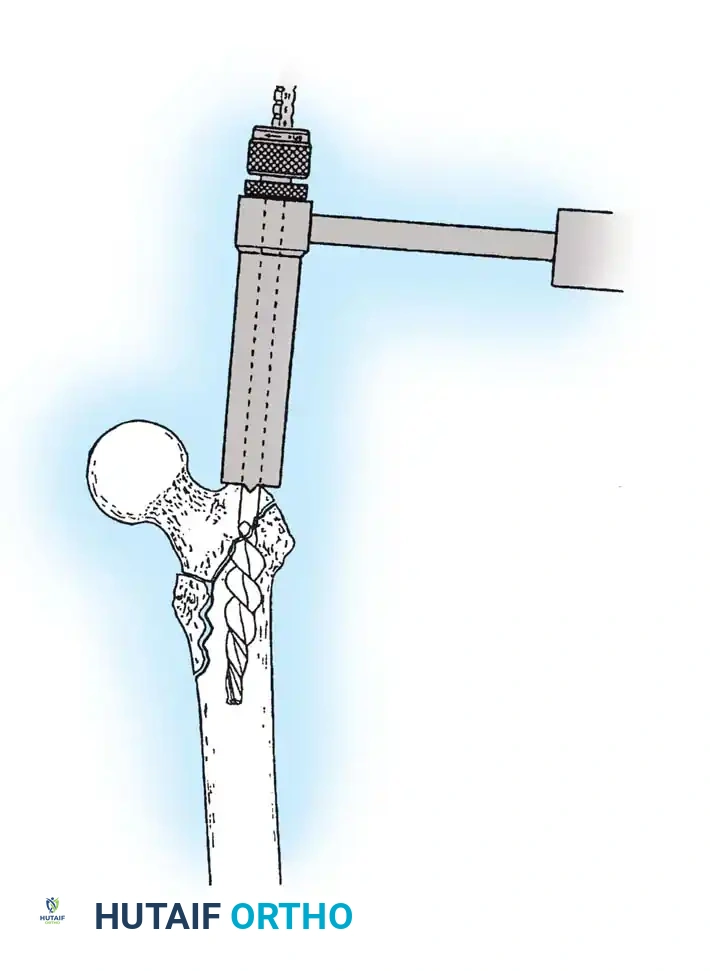

Insertion of the guide wire. The wire must be positioned centrally in the femoral head on both AP and lateral views.

The Tip-Apex Distance (TAD):

Described by Baumgaertner, the TAD is the sum of the distance from the tip of the lag screw to the apex of the femoral head on both the AP and lateral radiographs. A TAD of less than 25 mm is strongly predictive of successful fixation; a TAD > 25 mm significantly increases the risk of screw cut-out.

Reaming of the femoral neck and head over the precisely placed guide wire, preparing the channel for the lag screw.